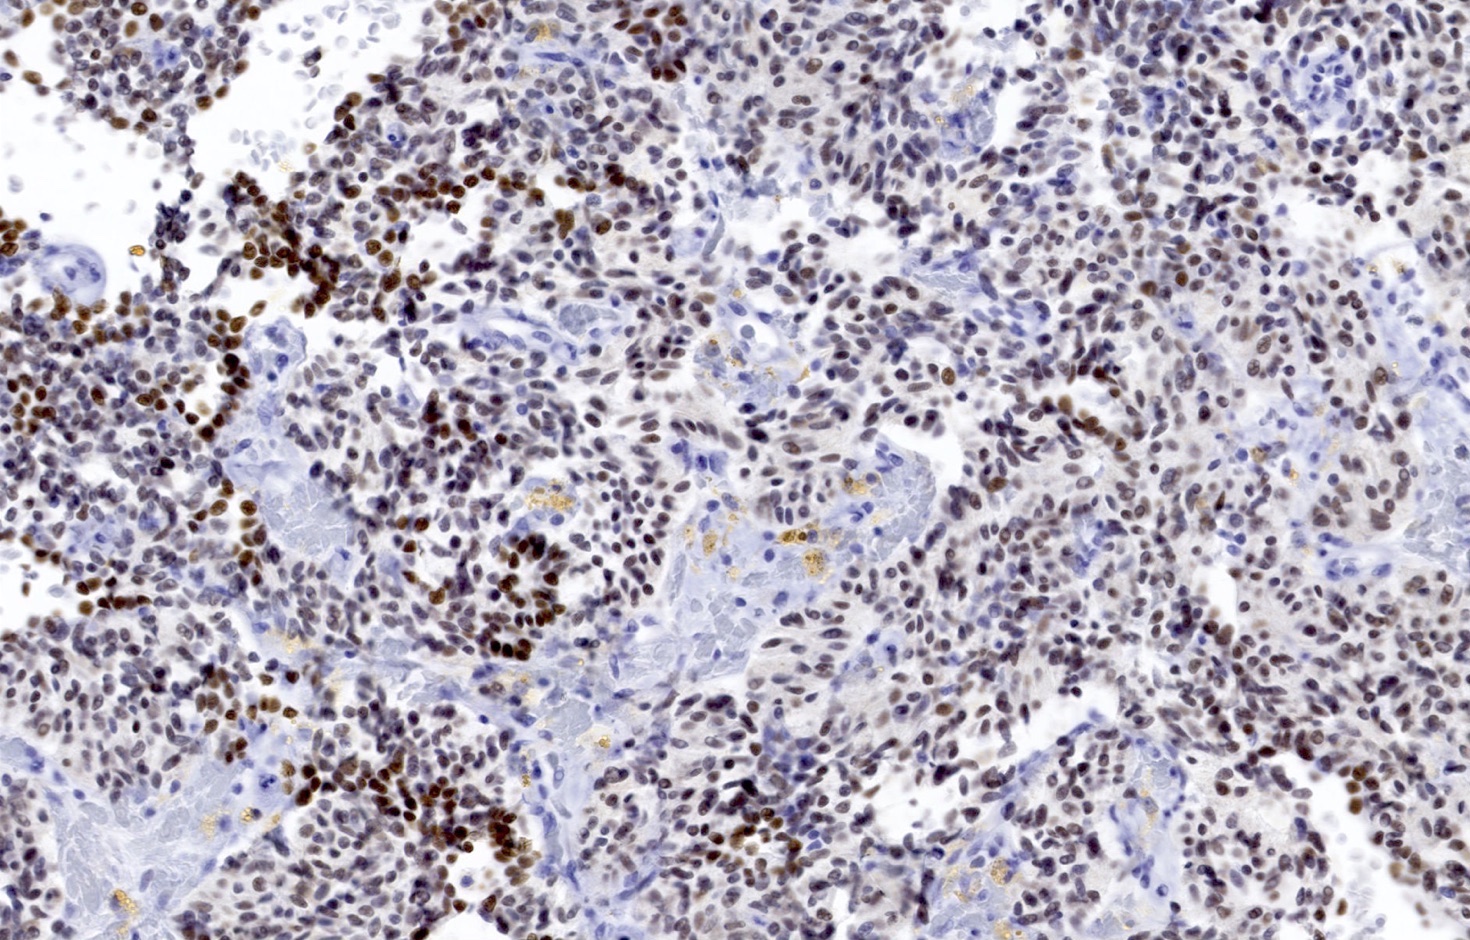

Contributed by Philippe Joubert, M.D., Ph.D., Jijgee Munkhdelger, M.D., Ph.D. and Andrey Bychkov, M.D., Ph.D.

- Chromogranin, synaptophysin, CD56 and INSM1: diffusely and strongly positive (Mod Pathol 2019;32:100)

- Ki67 (expected < 20%)

- Ki67 proliferative index does not have an impact on tumor classification; WHO classification states that is desirable to routinely report its value

- Mostly useful to discriminate between high grade neuroendocrine tumors (small cell carcinoma and large cell neuroendocrine carcinoma), on small or crushed biopsies in particular (Arch Pathol Lab Med 2018;142:947)

- Utility of differentiation between typical and atypical carcinoid is not proven (Virchows Arch 2017;470:153)